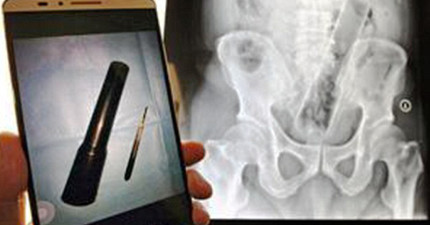

这名男子唱卡拉OK唱到麦克风跑到体内了…

August 13, 2015

世界